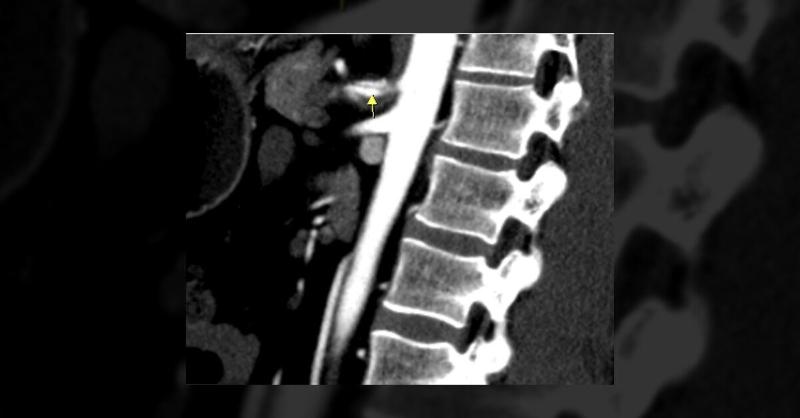

Abdominal Pain Reveals Celiac Artery Dissection in a Middle-Aged Patient

A 44-year-old male with no significant past medical history presented with a three-month history of chronic left upper quadrant abdominal pain. Family history was significant for hypertension in both parents, but neither the patient nor any other risk factor for arterial weakening was present. Vital signs were normal on admission. Physical examinat